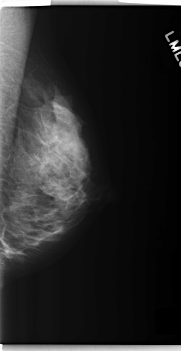

C_0279_1.LEFT_MLO

LEFT_MLO LINES 5960 PIXELS_PER_LINE 3064 BITS_PER_PIXEL 12 RESOLUTION 50 NON_OVERLAY